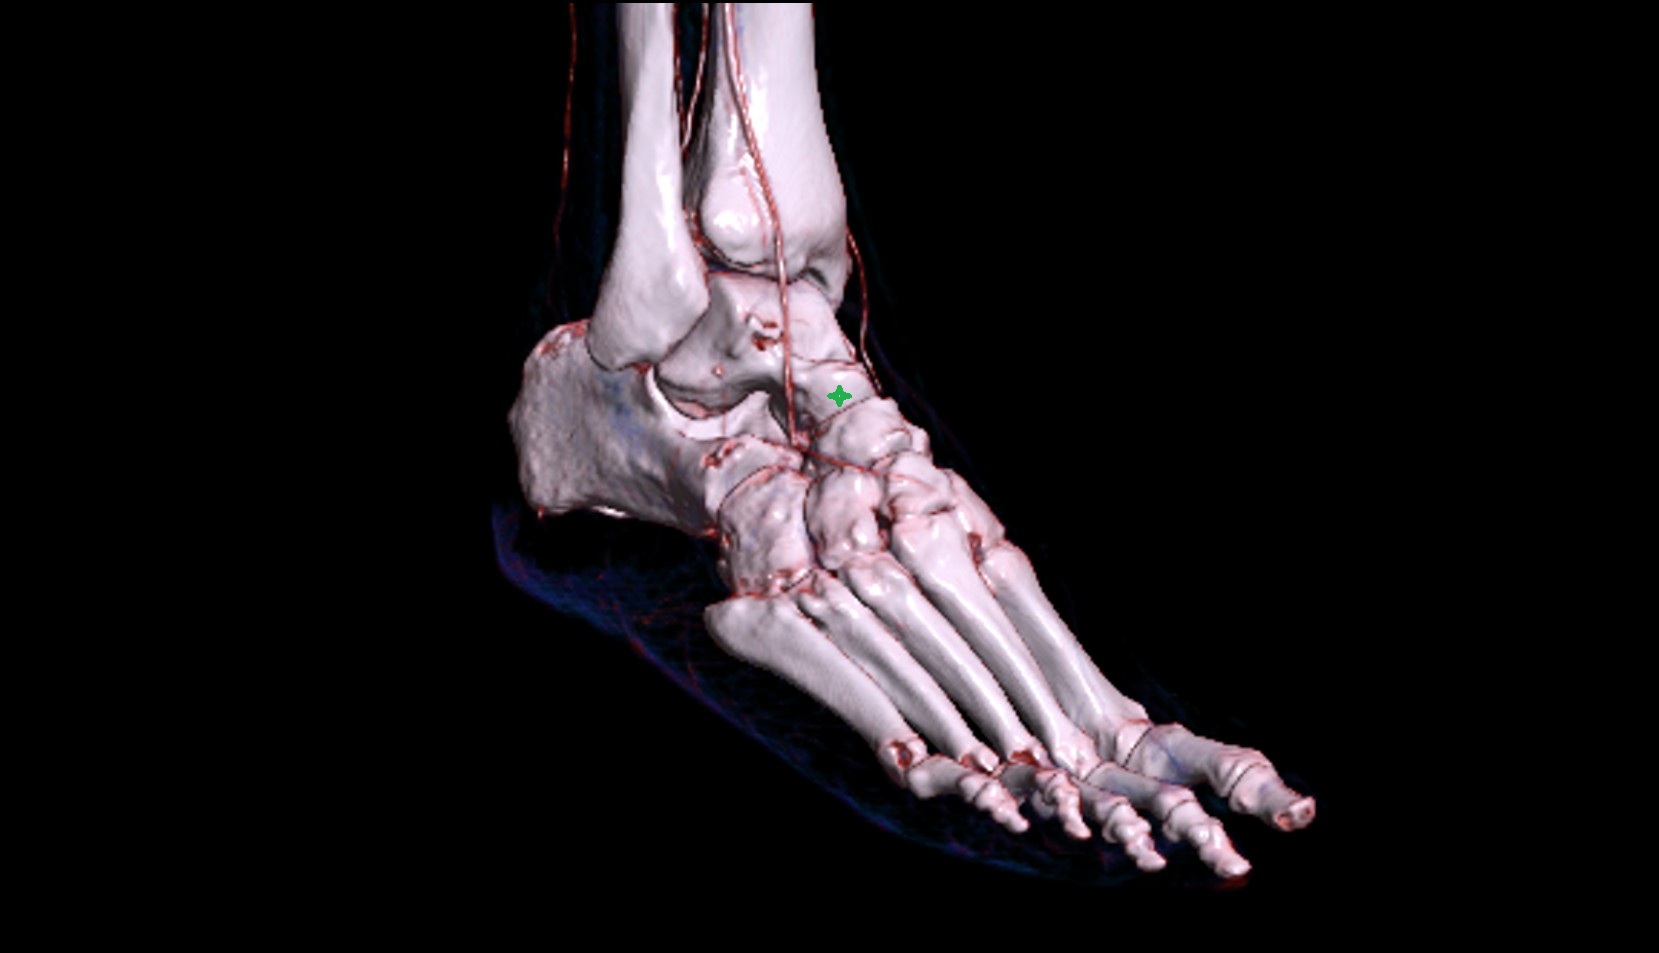

- Talus

- Head of talus

- Body of talus

- Neck of talus

- Calcaneus

- Cuboid

- Medial malleolus

- Lateral malleolus

- Ankle joint